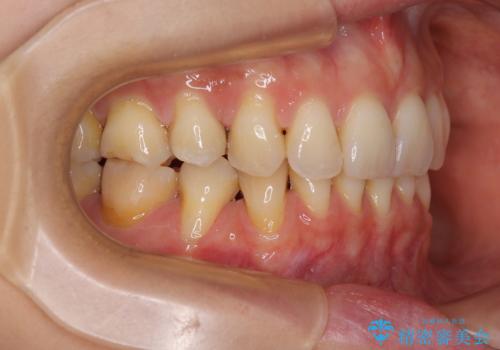

最新の症例

Latest cases